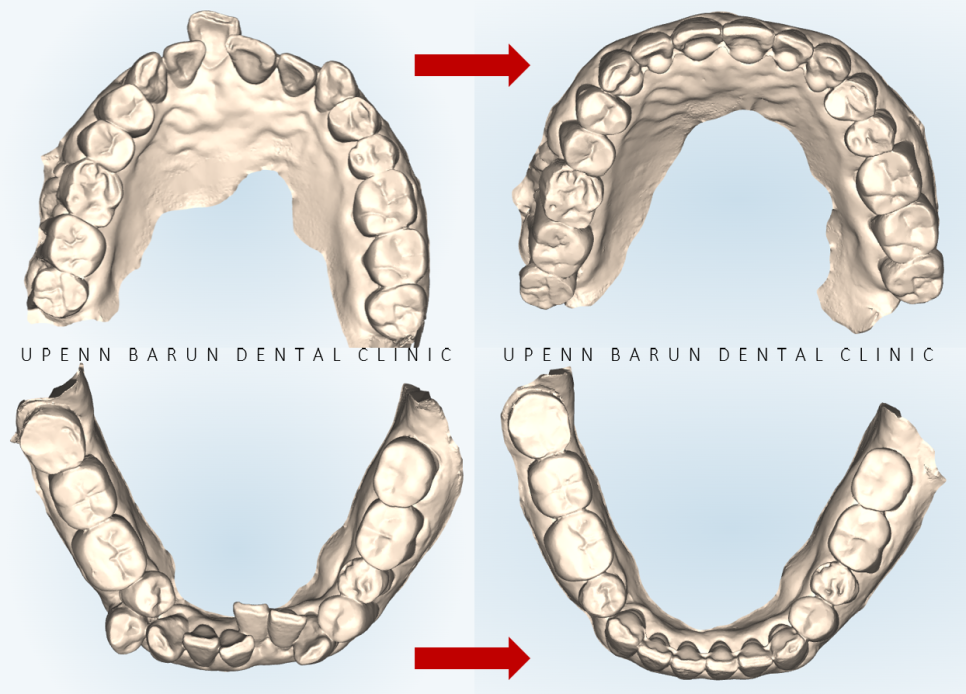

윗니의 경우

인비절라인의 '악궁확장' 기능을 이용해

발치 없이 교정을 진행해드렸습니다.

첫번째 클린체크에서 32개의 장치로 인비절라인을 진행해드렸는데요

튀어나와있던 앞니가 들어가고

안쪽으로 쓰러져 있던 아랫니 치아들이 모두 제 위치를 찾았습니다!!

2nd ClinCheck(19개)

두번째 클린체크는 19개의 장치를 통해

이전의 클린체크를 상호보완, 개선하여 마무리 해드렸습니다 :)

첫번째 클린체크에서 배열에 중점을 두었다면

두번째 클린체크에서는 교합을 개선시켜

윗니 아랫니들이

제 위치를 찾으며 정리가 되었습니다!!